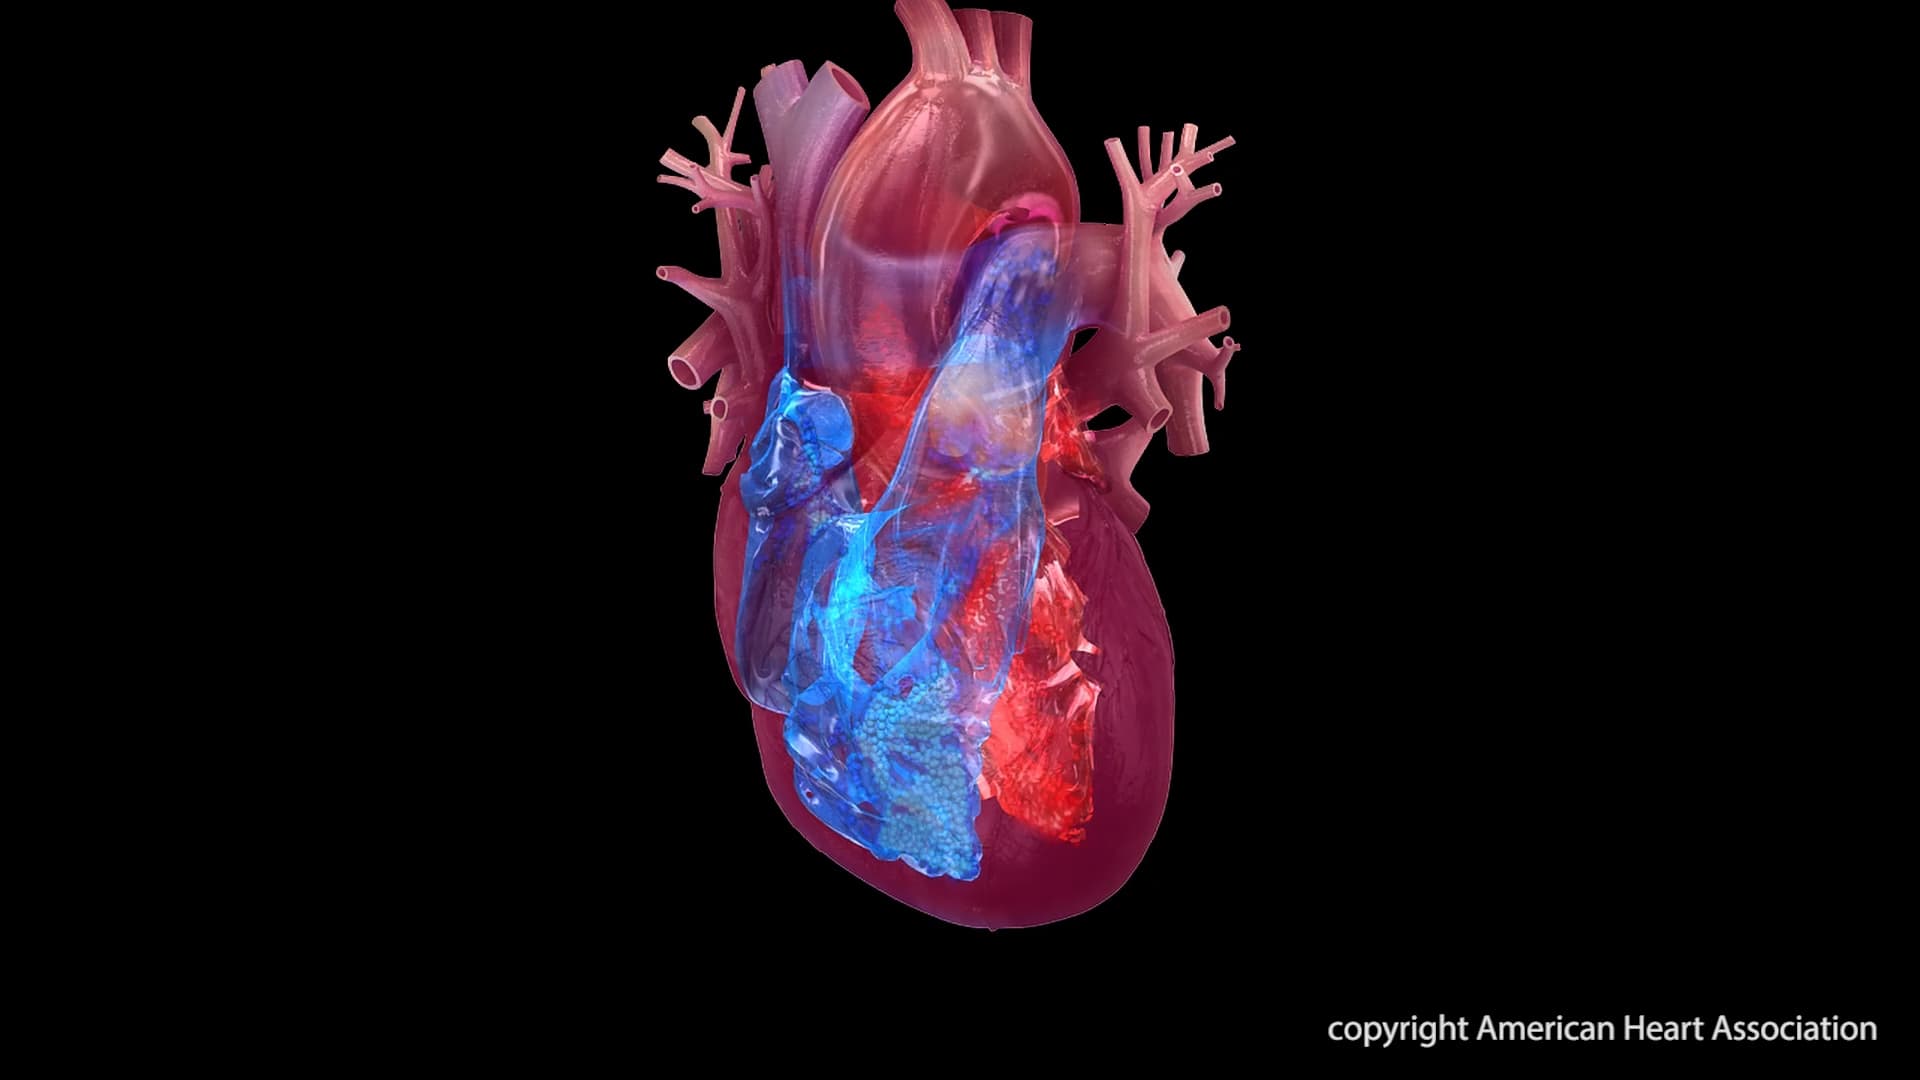

Research reveals a significant shift in heart disease deaths from heart attacks to heart failure, arrhythmias, and hypertensive heart disease, underscoring the impact of medical advancements and the need for continued focus on prevention and management of chronic conditions.

Over the past 50 years, heart disease death rates have seen a 66% decline, with heart attack deaths dropping by nearly 90%, according to a study published in the Journal of the American Heart Association. However, the types of heart disease leading to death have shifted, with increases in deaths from heart failure, arrhythmias, and hypertensive heart disease. This change reflects the success of public health measures and medical interventions that have extended lives but also highlights the growing challenge of managing chronic heart conditions.

The study analyzed U.S. Centers for Disease Control and Prevention data from 1970 to 2022, finding that while heart attacks accounted for 54% of heart disease deaths in 1970, this figure fell to 29% by 2022. In contrast, deaths from other heart conditions rose from 9% to 47% over the same period. Advances such as coronary artery bypass grafting, improved cardiac imaging, and the development of medications like statins and beta blockers have contributed to these trends. Despite these advancements, rising rates of obesity, Type 2 diabetes, and hypertension pose ongoing risks to heart health.

The American Heart Association emphasizes the importance of prevention through its Life’s Essential 8 measures, which include healthy eating, physical activity, and managing blood pressure and cholesterol. The study underscores the need for a continued focus on preventing heart disease and supporting healthy aging to address the evolving landscape of heart health challenges.